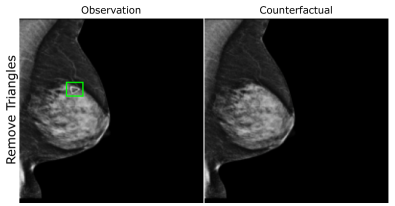

EMBED

Using prior insights, we apply our mechanisms to a real-world artefact removal task on the EMory BrEast imaging Dataset (EMBED) (Jeong et al., 2022). Schueppert et al. (2024) observe that triangular and circular skin markers are spuriously associated with breast cancer in classifiers due to shortcut learning (Geirhos et al., 2020), and manually labelled 22,012 affected mammograms. Using this dataset, we train a significantly scaled-up, amortised, anti-causally guided semantic mechanism () to remove skin markers. We model triangular markers (), circular markers (), breast density (), and cancer () as independent parents of the mammogram , and remove artefacts by intervening on and while holding and fixed. Figure 6 shows that our mechanisms effectively remove artefacts and can disentangle representations for triangles and circles. We successfully remove of triangles and of circles in our test set - a noteworthy result given the dataset’s small size and the scarcity of labelled skin markers (Appendix I).